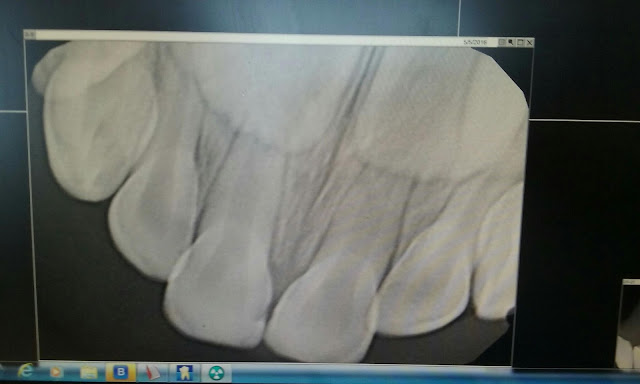

Well,  I took Oliver to the dentist. He got x-rays and it is cool because you can see his grown up teeth growing in in the x-rays! For some reason it never occurred to me that I would get a sneak peak of those.

Good news is that he did really great and liked getting all the fun toys and toothbrushes. Bad news,  he has a cavity,  maybe three! Seriously?!? It is the year of the cavities apparently. Eric just got five cavities fixed  (it has been like four years since he has been to the dentist and does have an extreme sweet tooth), I even had a cavity filled  (it was behind my concrete holding my retainer so I couldn't stop it if I tried-and it was a hard to detect, soft cavity). Now,  I guess it is Oliver's turn.  And he'll have to go under anesthesia.  He says there is for sure one cavity (can you see it on that front tooth? ) and maybe two others.  Hopefully this is the end of our dental bills for a while.